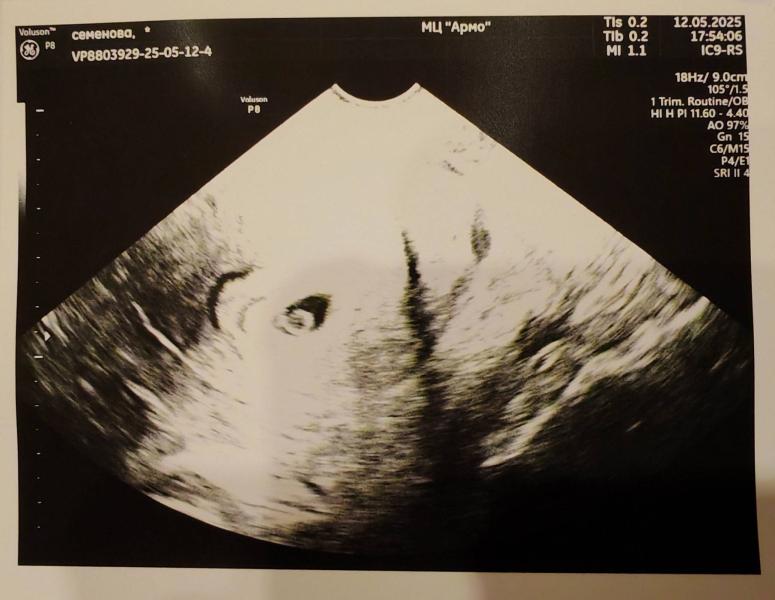

Сначало было так (1фото) через день с хгч было так (2фото) имеет место быть ошибка лаборатории, но это уже не важно... Потом через пару недель был уже эмбрион и 💗(3фото)

А щас мы уже очень выросли ☺️ ещё 7️⃣0️⃣ дней 😍💗